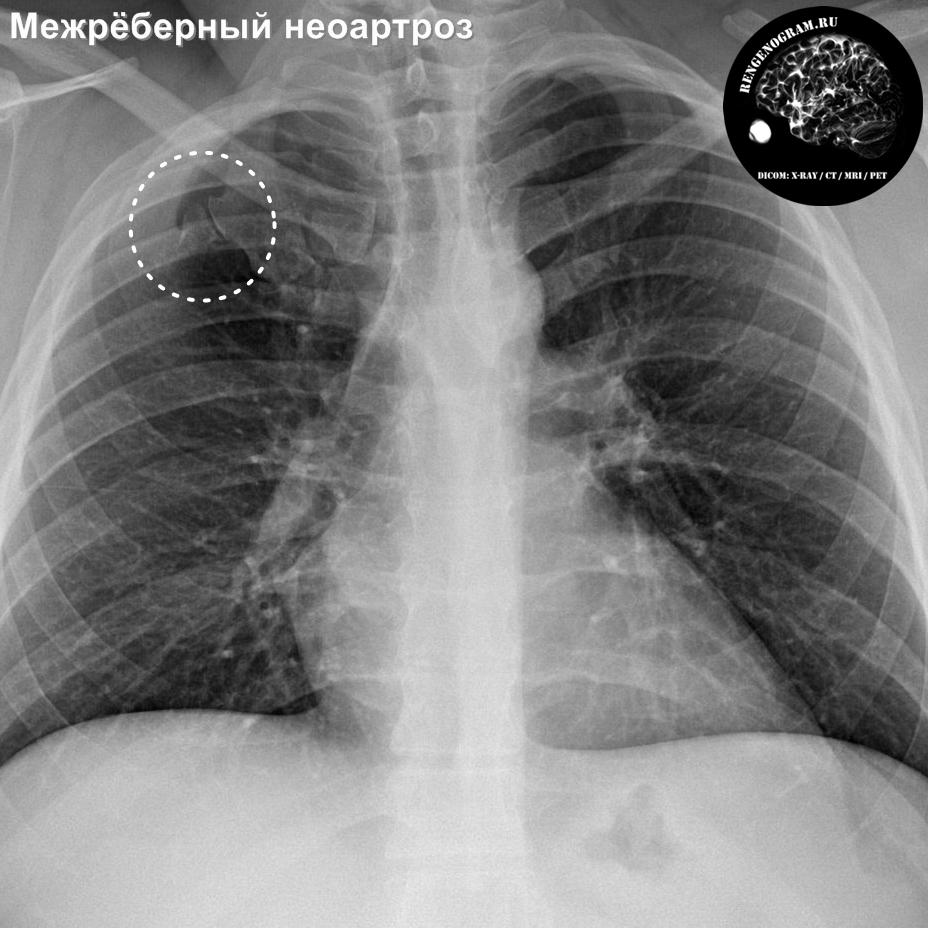

Рентгенологические изображения и синдромы патологии легких

Раздел: Кадры-подсказки